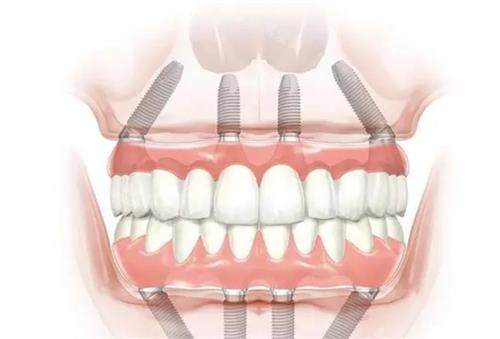

全口种植牙的示意图

全口种植